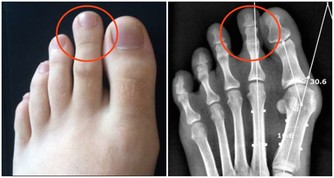

再加上長時間坐著,缺乏運動,容易患上營養失調的疾病。

從前得痛風、脂肪肝的大多是中老年人,這兩年越來越多二三十歲的年輕人,竟然也得上這些病了。